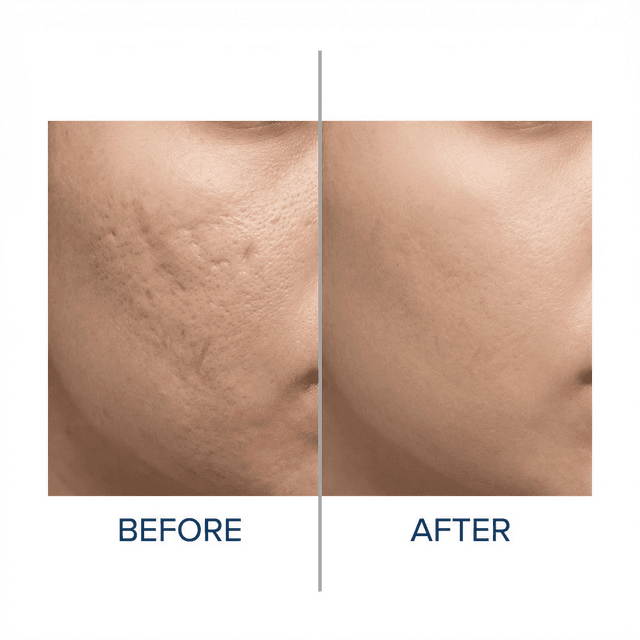

Microneedling for Acne Scars: Is It Safe for Teens?

Microneedling can improve acne scars, but it's not something most teenagers should rush into. Here's what you need to know about safety, timing, and realistic expectations.

Acne Scars vs. Acne Marks: The Difference Matters for Treatment

Most teens say 'scars' when they mean 'marks,' and the treatments are completely different. Marks are flat and fade on their own. Scars change the texture of your skin and usually need professional help. Here's how to tell which you have.

How to Prevent and Treat Acne Scars: A Complete Guide for Teens

Acne scars can feel permanent, but they don't have to be. Learn what types of scars exist, how to prevent them, and which treatments actually work for teen skin.